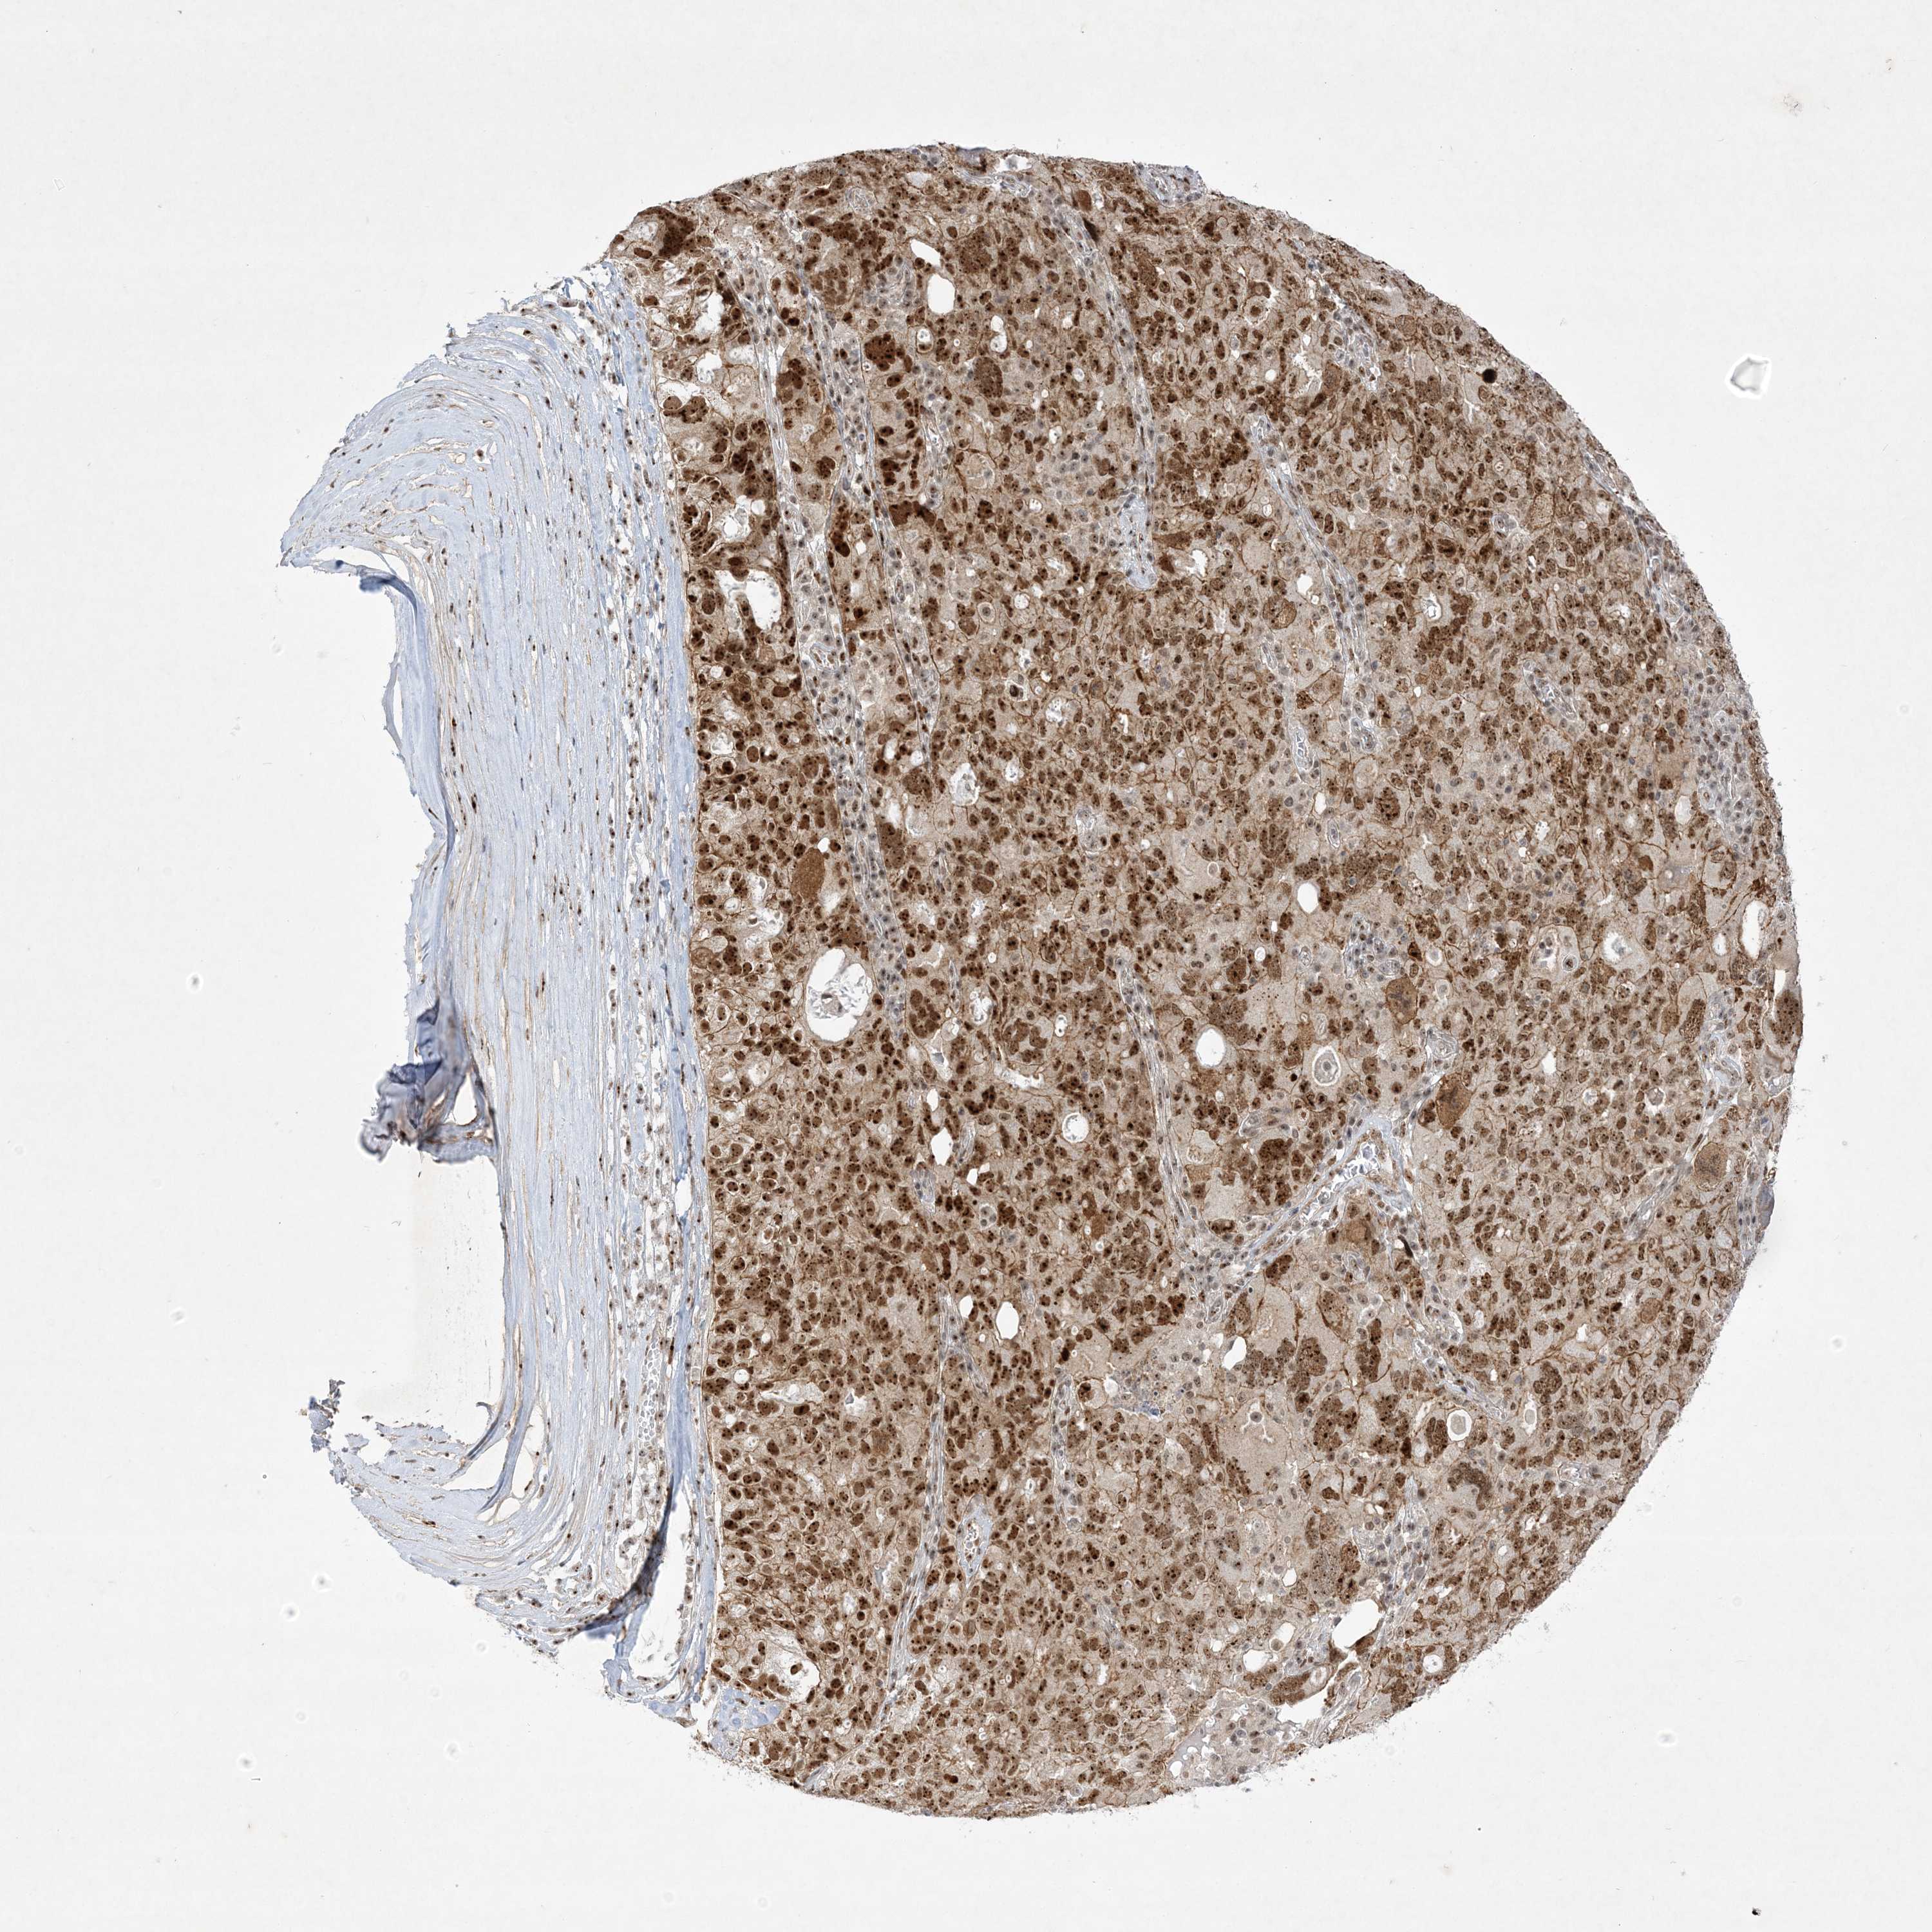

OVARIAN CANCER - Protein expressioni

A mouse-over function shows sample information and annotation data. Click on an image to view it in a full screen mode. Samples can be filtered based on level of antibody staining by selecting one or several of the following categories: high, medium, low and not detected. The assay and annotation is described here.

Note that samples used for immunohistochemistry by the Human Protein Atlas do not correspond to samples in the TCGA dataset.

Antibody stainingi

Antibody staining in the annotated cell types in the current human tissue is reported as not detected, low, medium, or high, based on conventional immunohistochemistry profiling in selected tissues. This score is based on the combination of the staining intensity and fraction of stained cells.

Each image is clickable and will lead to virtual microscopy that enables deeper exploration of all samples and also displays staining intensity scores, fraction scores and subcellular localization as well as patient and tissue information for each sample.

Antibody HPA036295

Antibody HPA036296

Staining

High

Medium

Low

Not detected

Intensity

Strong

Moderate

Weak

Negative

Quantity

>75%

75%-25%

<25%

None

Location

Nuclear

Cytoplasmic/membranous

Cytoplasmic/membranous,nuclear

Cystadenocarcinoma, serous, NOS

Carcinoma, endometroid

Cystadenocarcinoma, mucinous, NOS

Carcinoma, NOS